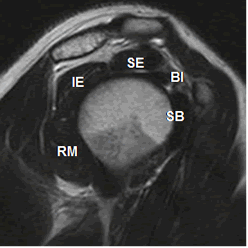

Fig 17. Tendones normales del manguito rotador.

RM sagital en T2. SE: Supraespinoso. IE: Infraespinoso. SB: Subescapular. RM: Redondo menor. BI: Cabeza larga del bíceps.